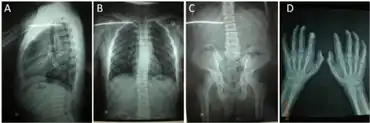

Symptoms of ML III are often not noticed until the child is 3–5 years of age. Patients with ML III are generally of normal intelligence (trait) or have only mild mental retardation. These patients usually have skeletal abnormalities, coarse facial features, short height, corneal clouding, carpal tunnel syndrome, aortic valve disease and mild enlargement of organs. Some children with severe forms of this disease do not live beyond childhood. However, there is a great variability among patients - there are diagnosed individuals with ML III living in their sixties.